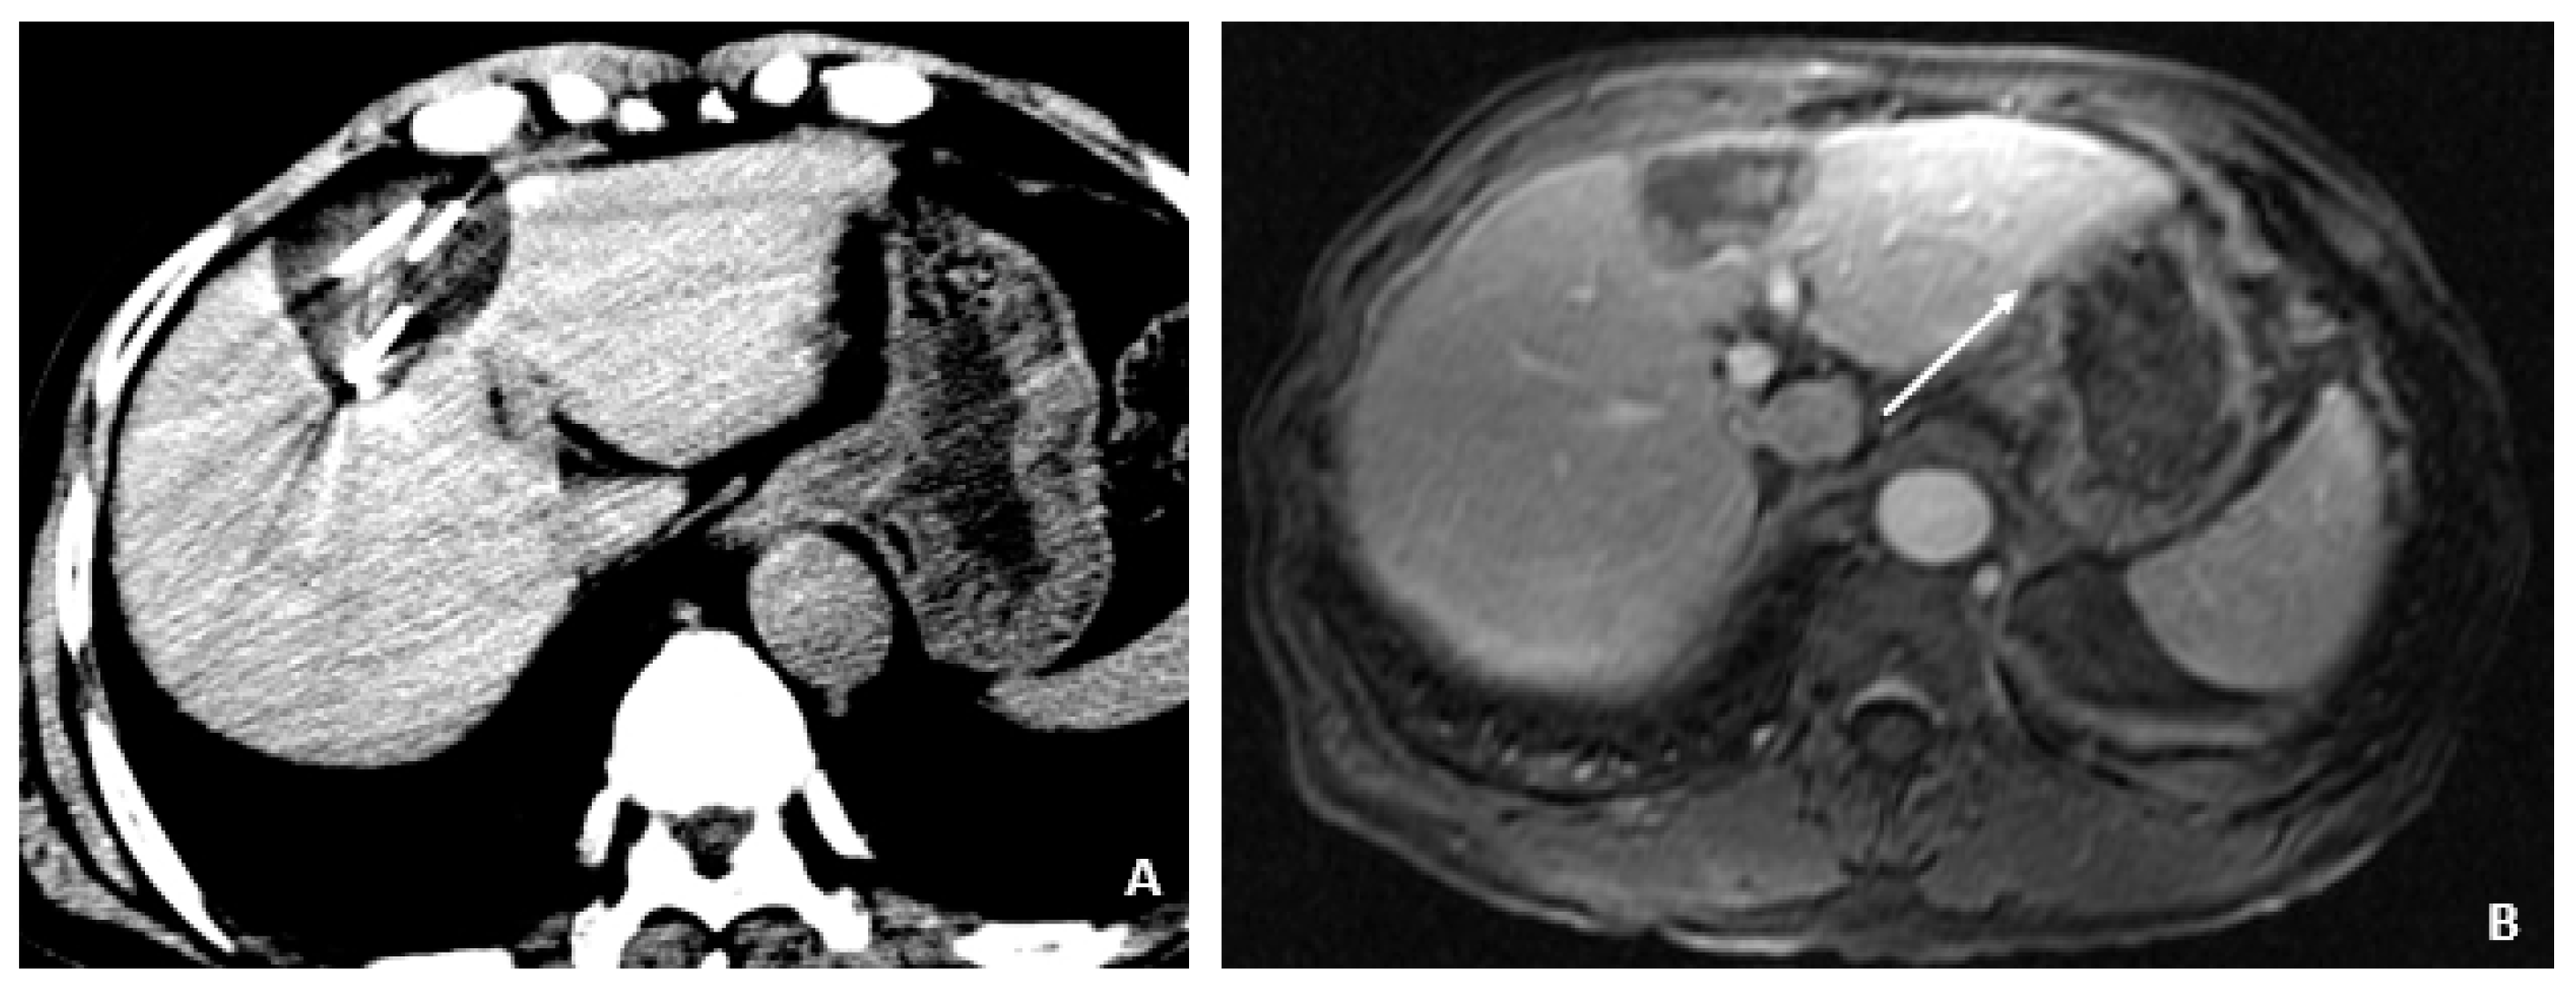

A 50-year-old male was diagnosed with CHB at age 40. With lamivudine treatment for 3 years, he achieved HbsAg seroconversion to anti-HBs and lamivudine was discontinued. Table 4 outlines his course. Five years later, on a follow up examination he was found to have HBV DNA 847 copies/mL, ALT 33 IU/L, and AFP 20.5 ng/mL. An MRI (December 2009) showed a 5 cm lesion consistent with HCC (Figure 1A,B). Repeat AFP was 17.8 ng/mL at time of HCC diagnosis, and AFP-L3% was 75.6. He underwent transarterial chemoembolization (TACE) with successful resolution (Figure 2A,B) and restarted lamivudine. The AFP remained at 3.0 ng/mL, and the MRI showed no evidence of HCC the following year. Two years after initial treatment, the AFP increased to 5.9 ng/mL with 57.5% L3. The MRI next month showed recurrent HCC at the treated site (Figure 3). The patient underwent laparoscopic radiofrequency ablation and therasphere treatment.

Subsequent %L3 AFPs remained persistently high with minimally elevated total AFP levels, which indicated recurrent/progressive HCC.

These cases also demonstrate the utility of AFP-L3% for monitoring for recurrence in patients who have had HCC treated. This is demonstrated nicely in Case 4, as the AFP value and AFP-L3% came down significantly after TACE treatment in concordance with imaging findings indicating resolution of HCC. This resolution was followed by an abrupt and significant rise in AFP-L3% (57.5% from 0.5%), which was associated with a relatively smaller and nonspecific rise in the absolute value of AFP (5.9 ng/mL from 2.5 ng/mL) with subsequent imaging findings consistent with recurrent HCC.

Figure 3. Recurrent HCC 2 Years Later (April 2011). (A) The contrast-enhanced CT image shows a hyperenhancing lesion in the left lobe (arrows) with adjacent tumor thrombus within the portal vein (dashed arrow). (B) The subsequent axial T1-weighted fat-suppressed postcontrast MRI image shows the lesion (arrows) to a slightly better advantage, along with the portal vein tumor thrombus (dashed arrow). (C) The diffusion-weighted image shows marked hyperintensity (arrow) within the left lobar mass, corresponding to diffusion restriction, typical of malignant tumors.